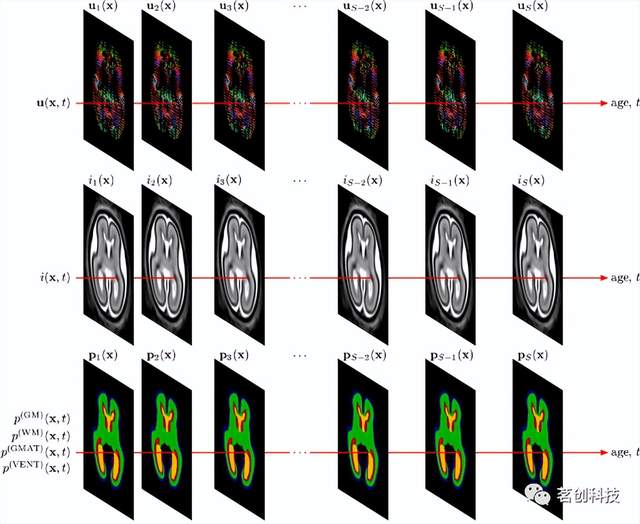

发育中胎儿大脑的多通道4D概率图谱

这是一个由80名大脑正常发育的胎儿构建而成的时空图谱,扫描时胎龄在21.7到38.7周之间。可下载的图谱包括组平均的T2加权图像模板和脑膜、皮层、半球、脑脊液和脑室的组织概率图,适用于23到37周的胎儿。采用基于概率图谱先验的自动组织分割算法创建组织概率图。

来源:Construction of a consistent high-definition spatio-temporal atlas of the developing brain using adaptive kernel regression.

高分辨率的新生儿大脑时空图谱

该图谱是胎儿图谱“发育中胎儿大脑的多通道4D概率图谱”的扩展,用于扫描矫正胎龄后28至44周的新生儿大脑。该图谱由来自204名早产新生儿的组平均T1和T2加权MRI模板组成。生成的4D图谱很好地反映了大脑整体和局部的变化。该模板还包括发育中大脑的87个标记结构。使用ALBERT多图谱作为先验知识用于图像分割。

Construction of a consistent high-definition spatio-temporal atlas of the developing brain using adaptive kernel regression.

UNC纵向0-3-6-9-12个月大的婴儿图谱

这是一组典型的0、3、6、9和12个月大的婴儿时空图谱,由35名健康婴儿组成,这些婴儿每三个月进行一次纵向扫描,直到一岁。该图谱由组平均T1和T2加权图像组成,其中包括灰质、白质和脑脊液的组织概率图。其主要意义在于同时引入了时间和空间约束,以生成具有丰富结构细节和纵向一致性的图集。纳入了3个月、6个月和9个月的图谱有助于分析婴儿MRI,因为在生命的第一年,大多数大脑区域的灰质和白质之间的T1和T2加权对比度仍然很差。

来源:Consistent spatial-temporal longitudinal atlas construction for developing infant brains.